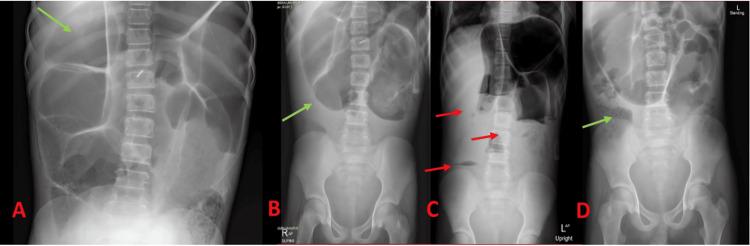

Acute colonic pseudo-obstruction, also known as Ogilvie's syndrome, is a rare but critical cause of abdominal pain and distension, potentially mimicking mechanical obstruction or toxic megacolon. Patients with sickle cell disease (SCD) have additional risk factors such as vaso-occlusive crises, chronic hemolysis, and susceptibility to infections, which further complicate diagnosis. We report the case of a 14-year-old male patient with SCD who presented with severe generalized abdominal pain, vomiting, and progressive distension with no fever. Imaging revealed significant colonic dilation and pneumatosis, suggesting pseudo-obstruction or ischemic bowel. Infectious evaluations ultimately identified enteropathogenic Escherichia coli. Despite initial concern for toxic megacolon, a multidisciplinary evaluation by hematology, gastroenterology, infectious disease, and surgery confirmed acute colonic pseudo-obstruction associated with enterocolitis. The patient's condition was managed nonoperatively with nasogastric decompression, intravenous antibiotics, total parenteral nutrition, and prokinetic agents. Serial imaging demonstrated gradual improvement in colonic distension, facilitating a safe return to oral feeding and subsequent discharge. This case underscores the importance of early recognition of enterocolitis-associated colonic pseudo-obstruction in patients with SCD, highlighting the value of comprehensive infection screening and a careful, multidisciplinary management approach to avoid unnecessary surgery and improve outcomes.

急性结肠假性梗阻,又称奥吉尔维综合征,是一种罕见但严重的腹痛和腹胀病因,可能酷似机械性肠梗阻或中毒性巨结肠。镰状细胞病(SCD)患者有额外的危险因素,如血管闭塞性危象、慢性溶血和易感染性,这使诊断更加复杂。我们报告一例14岁男性SCD患者,表现为严重的全身性腹痛、呕吐和进行性腹胀,无发热。影像学检查显示结肠显著扩张和气肿,提示假性梗阻或缺血性肠病。感染性评估最终确定为致病性大肠杆菌。尽管最初担心是中毒性巨结肠,但血液学、胃肠病学、传染病学和外科的多学科评估证实为与小肠结肠炎相关的急性结肠假性梗阻。患者病情通过鼻胃减压、静脉抗生素、全胃肠外营养和促动力药物进行非手术治疗。系列影像学检查显示结肠扩张逐渐改善,有助于安全恢复经口喂养并随后出院。该病例强调了早期识别SCD患者中与小肠结肠炎相关的结肠假性梗阻的重要性,突出了全面感染筛查以及谨慎的多学科管理方法对于避免不必要手术和改善预后的价值。